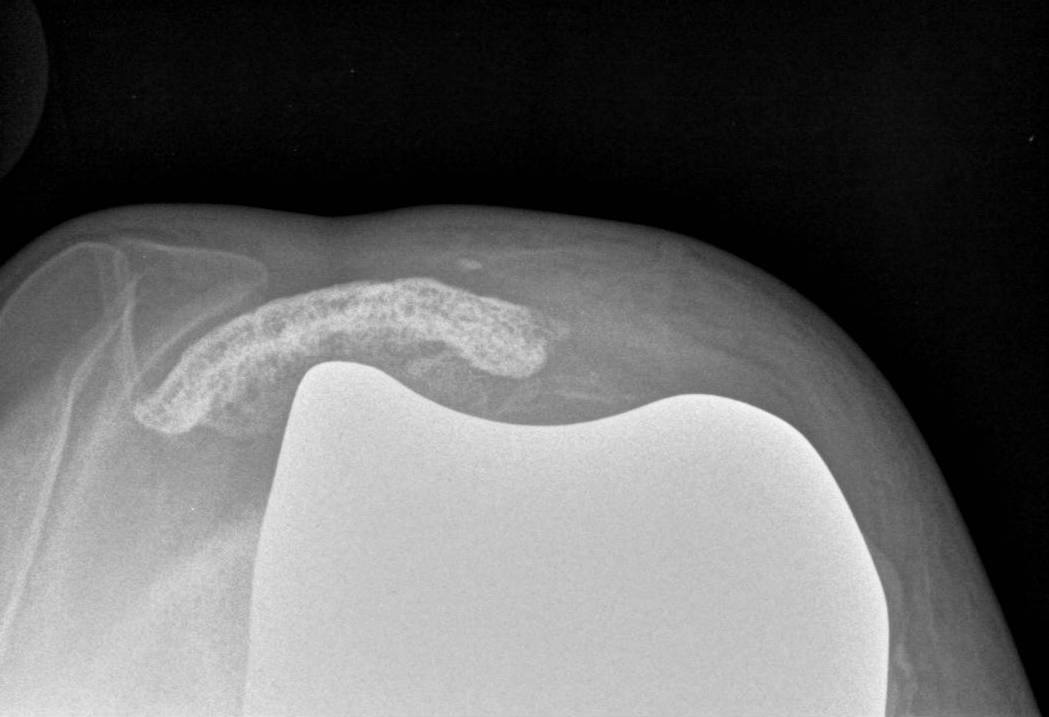

Patella

Options

1. > 10 mm bone remaining

- can resurface

2. Ignore